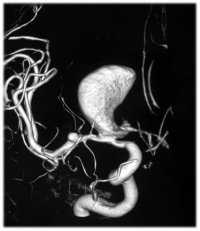

Лечение крупных и гигантских аневризм

Выключение гигантской аневризмы ВСА

с использованием методики ВАК

Хирургическое лечение крупных и гигантских аневризм — один из самых сложных вопросов сосудистой нейрохирургии. В 70-е годы оперативное пособие у таких больных ограничивалось перевязкой внутренней сонной артерии на шее, при этом послеоперационная летальность составляла 15,2%. С появлением эндовазальной техники стало возможным проведение баллон-окклюзионного теста под контролем ЭЭГ с последующей стационарной окклюзией ВСА. В отдельных случаях данный способ лечения комбинировали с наложением ЭИКМА, однако, послеоперационная летальность в группе гигантских аневризм оставалась высокой. С 1995 года в институте разработана и используется методика внутрисосудистой аспирации крови из аневризмы. Методика ВАК показала себя весьма эффективной в хирургии крупных и гигантских аневризм ВСА, позволила в 4 раза уменьшить послеоперационную летальность и значительно сократить группу больных, которым отказано в хирургическом лечении. В настоящее время отделение располагает самым большим опытом в мире по применению методики ВАК.

Выключение крупной аневризмы с помощью

установки потоко-направляющего стента

Наряду с прямыми вмешательствами, на протяжении многих лет для лечения крупных и гигантских аневризм в институте использовались и эндоваскулярные методы. До появления стент-ассистенции и потоконаправляющих стентов, добиться полного выключения таких аневризм спиралями удавалось редко. Появление стентов существенно изменило возможности эндоваскулярного лечения крупных и гигантских аневризм. С момента использования потоконаправляющих стентов произошло существенное снижение доли деконструктивных операций. Несомненно, что эта технология имеет большие перспективы и в ближайшем будущем существенно изменит структуру эндоваскулярных вмешательств при лечении аневризм в целом.